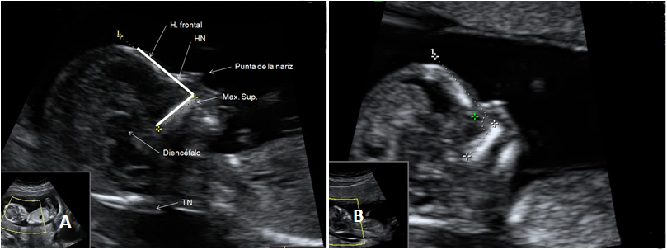

La ecografía Doppler permite comprobar el flujo sanguíneo en el feto y en el cordón umbilical, y así diagnosticar algunas enfermedades o malformaciones cardiacas, entre otras cosas.

Flujo patológico en el conducto venoso